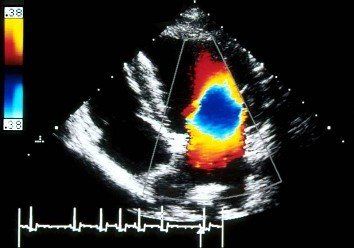

Die Ultraschalluntersuchung des Herzens erfordert neben einem High-End-Gerät mit der Möglichkeit zur Doppler-Untersuchung ein hohes Maß an Fachwissen und Erfahrung vom Untersucher. Aus diesem Grund werden die kardiologischen Untersuchungen in unserer Praxis von Tierärztin Claudia Leysik durchgeführt. Sie ist General Practitioner Certificate in Cardiology und besucht unsere Praxis in regelmäßigen Abständen, so dass wir Ihrem Tier lange Fahrt- und Wartezeiten ersparen können.